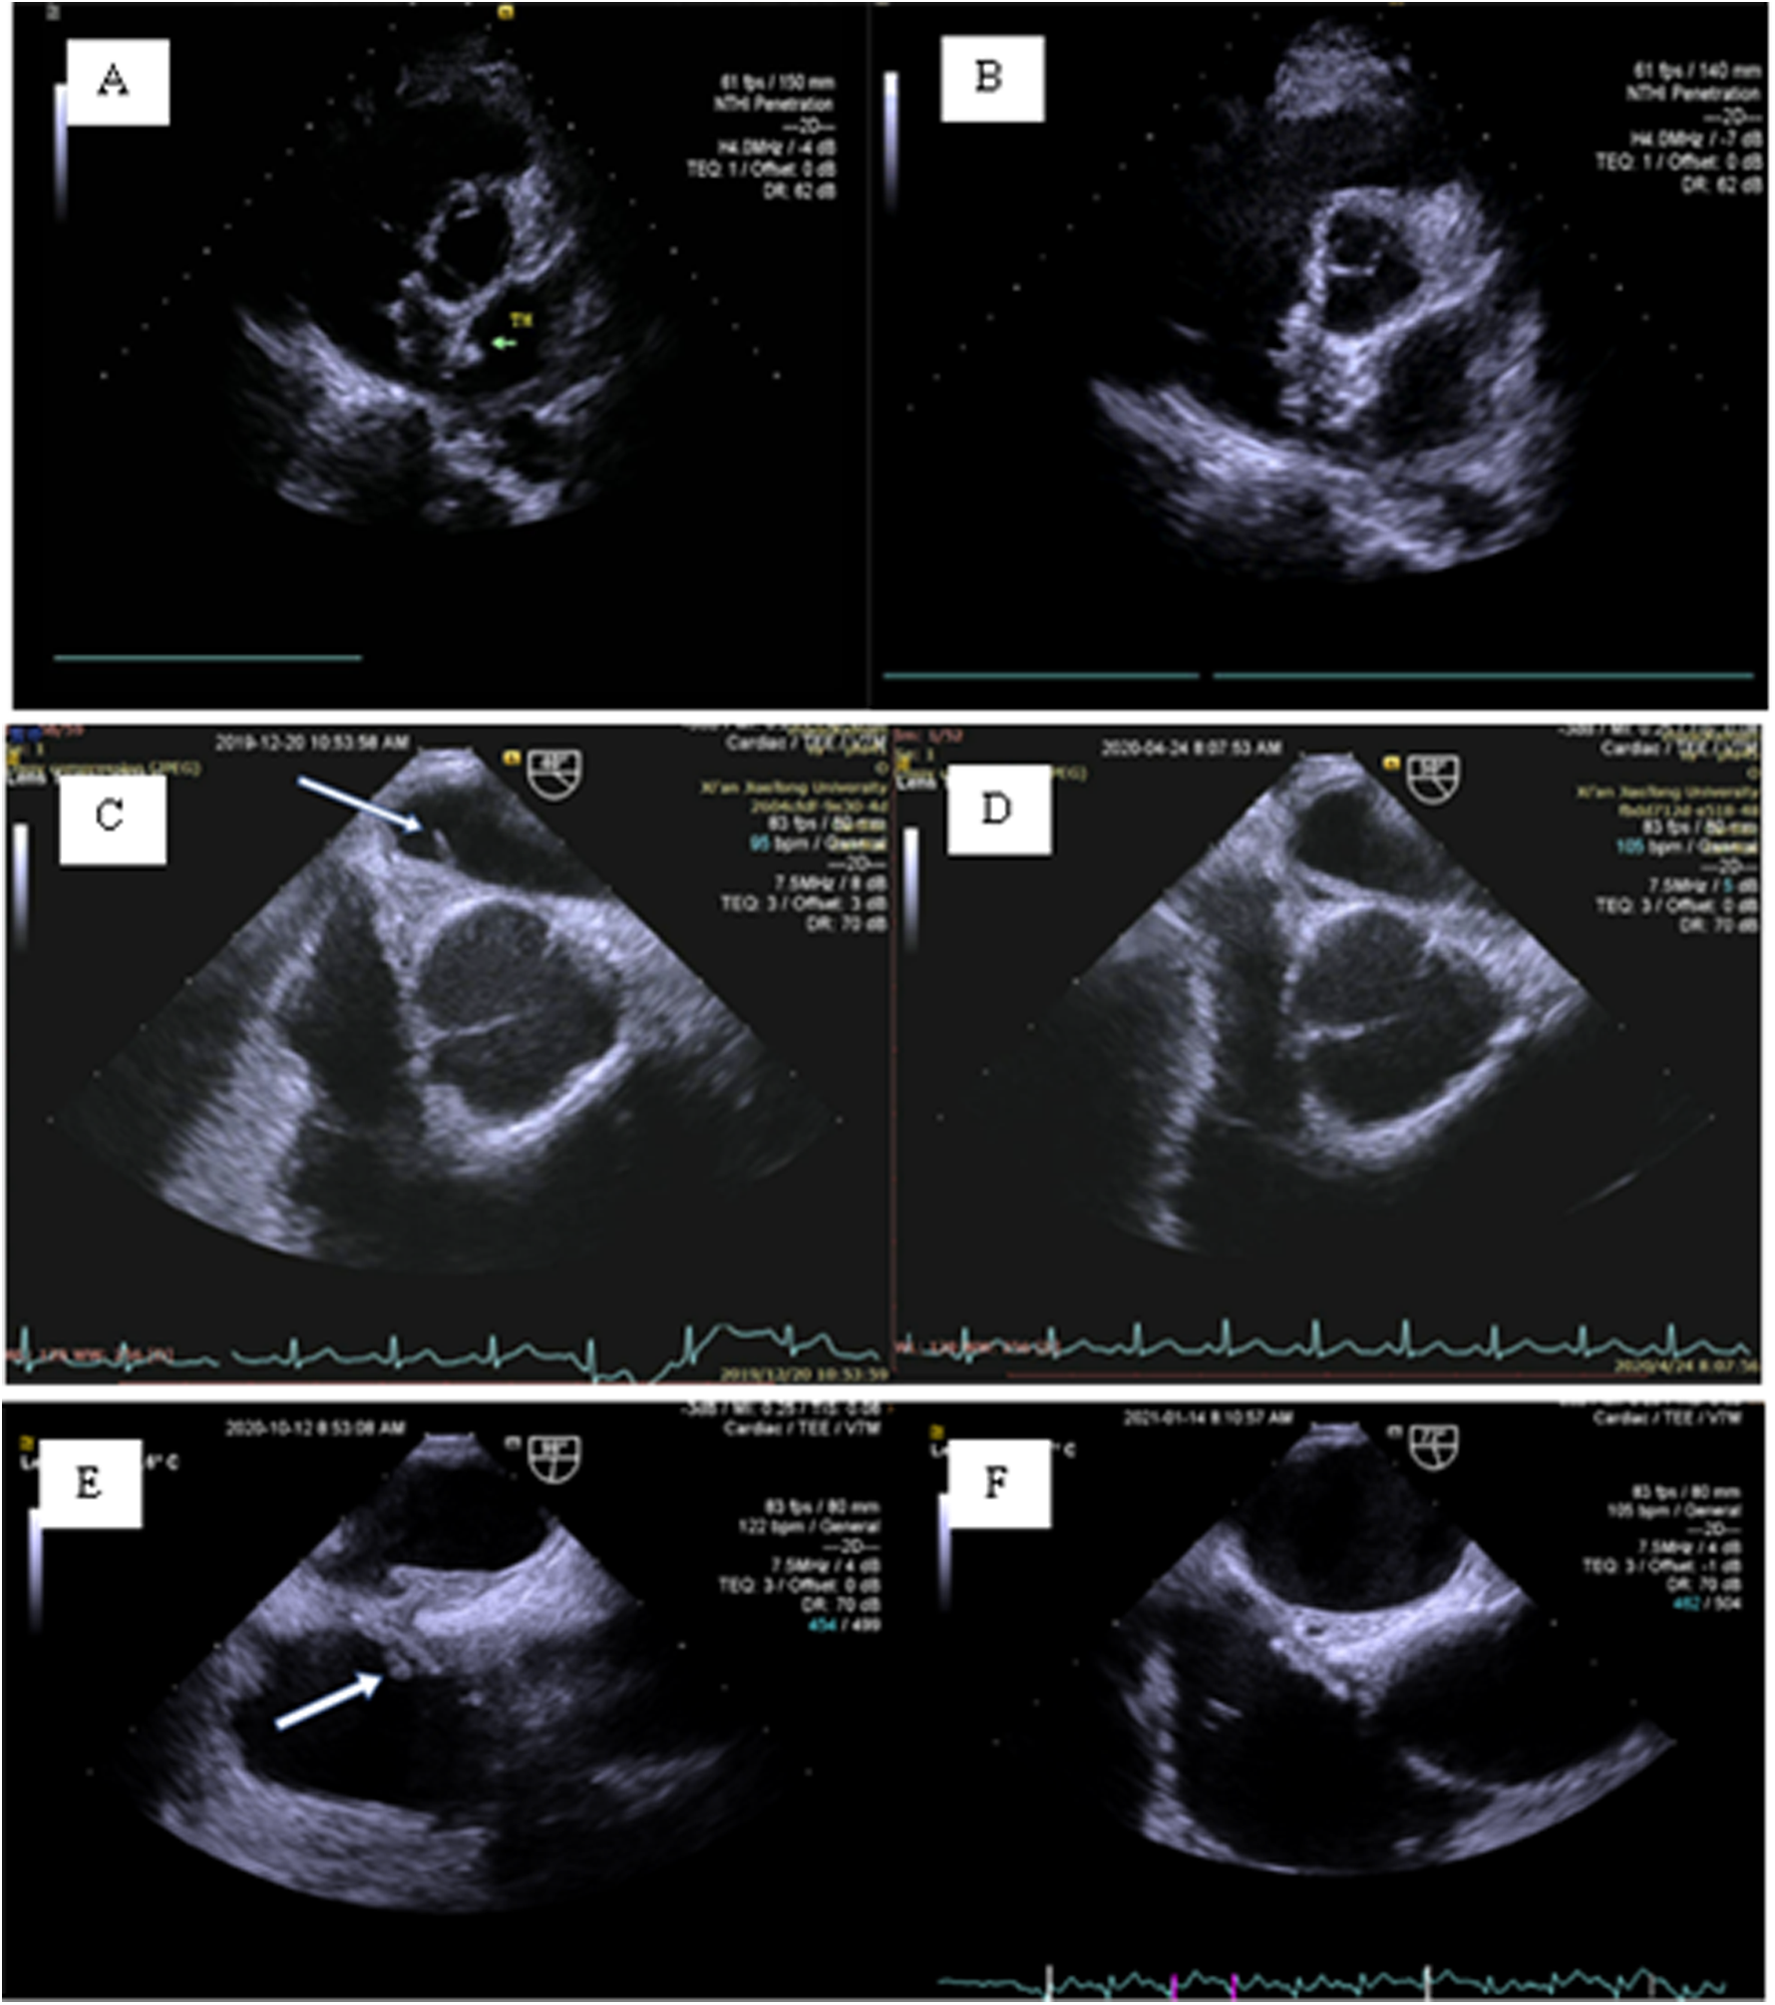

One case of DRT was located on the left disk of the occluder at the 3-month follow-up by TTE. The other two cases of DRT were found atthe 6-month follow-up by TEE. For all of the above patients, rivaroxaban 20 mg/day was immediately given orally, and TEE re-examination after 1 month of treatment showed that the DRT disappeared. The specific DRT situation is shown in Figure 5.

Figure 5

Postprocedure DRT. (A,B) A 42-year-old female: At the 3-month follow-up, TTE revealed a thrombus on the left disc of the occluder (green arrow). (C,D) A 45-year-old female: At the 6-month follow-up, TEE revealed an abnormal cord-like echo (7.4 × 1.7 mm) on the left disc of the occluder (white arrow). The follow-up medical history revealed that the patient was hit by a stone on her foot approximately 20 days after the procedure, and a red bruise appeared under the skin. The patient discontinued aspirin and clopidogrel by herself and concealed the history of discontinuation during the 3-month follow-up. (E,F) A 38-year-old female: At the 6-month follow-up, TEE revealed an abnormal strip of shadow on the right disc of the occluder (white arrow).

At 48 h, 1month, 3 months, 6 months and 12 months post-procedure follow-up, TTE examination showed that all137 patients (100%) had no left-to-right shunt (LRS). At the 6-month follow-up, cTTE/cTCD examination showed that 4 patients (2.9%) had a small amount of RLS after VM, 27patients (19.7%) still had medium to substantial rRLS after VM, and the remaining 106 patients (77.4%) had no rRLS. Further analysis found 8 cases (5.8%) of rRLS at the pulmonary arteriovenous level. Although the remaining 19 cases (13.9%) of rRLS were medium to substantial, the amount of RLS was significantly reduced compared with the preoperative state. Among the above mentioned patients with medium to substantial rRLS, only 4 patients (2.9%) had medium to substantial rRLS after VM when the cTTE/cTCD was re-examined at the 12-month follow-up. TEE was performed in4 patients with medium to substantial rRLS at the 12-month follow-up. Detailed information is shown in Figure 6.

Figure 6

TEE examination of medium to substantial rRLS. (A,B) A large PFO (4.5 mm) with a long tunnel (13.5 mm) was implanted with a 30/30 mm PFO occluder. The left disc was degraded to 8 mm and did not completely cover the left side of the PFO. A tunnel-like channel was formed in the occluder. (C,D) A PFO with a small ASD; the device achieved closure of the PFO and retained the small ASD. On 2D-TEE, the small ASD was not clearly displayed. Color Doppler flow imaging showed a transseptal shunt through the small ASD.